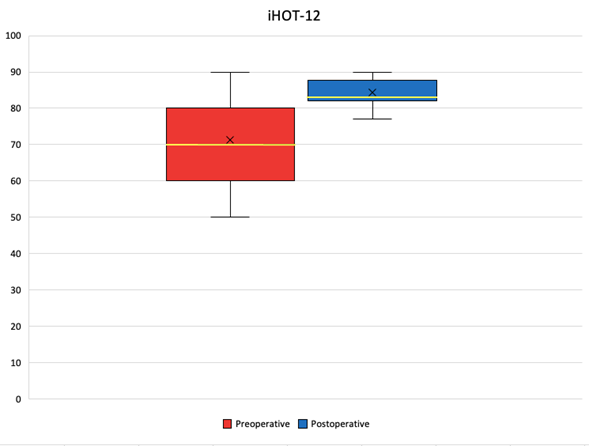

A total of twelve patients (15 hips), who met the required criteria were chosen for GM repair. All of them were women with an average age of 56.66 years (42-70). The mean follow-up period was 11 months (4-24). The demographic data is illustrated in Table 1. The median mHHS improved from 68 points (interquartile range [IQR], 59, 68 points) preoperatively to 82 points (IQR, 76, 88 points) at the latest follow-up (p=0.001) Table 2, Graphic 1. According to the mHHS score, 7% obtained excellent results (>90), 67% had good results (80-89), 26% fair results (70-79), and 0% had poor results (<70) Graphic 2. The median iHOT-12 score also improved from 70 points (IQR, 60, 80 points) preoperatively to 83 points (IQR, 82, 88 points) at the latest follow-up (p=0.001) Table 2, Graphic 3. There was a significant improvement (p<0.001) in the median VAS score in the total sample from 6 (IQR, 6, 7) preoperatively to 2 (IQR, 2, 5) postoperatively Table 2, Graphic 4. At the latest follow-up, 8 (66%) patients reported being very satisfied, 4 (33%) satisfied. During follow-up, there were no complications related to the surgical procedure. In the 3-month MRI study, all patients showed healing of the partial lesion of the GM tendon. Additionally, all patients presented a negative Trendelenburg test at the end of postoperative follow-up.

Graph 1 mHHS preoperative and postoperative outcomes.

The median mHHS was 68 points (IQR, 59, 68 points) preoperatively and 82 points (IQR, 76, 88 points) postoperatively. The x indicates the mean, the yellow line indicates the median, the box indicates the IQR, and the whiskers indicate the range.

Graph 3 iHOT-12 preoperative and postoperative outcomes.

The median iHOT-12 was 70 points (IQR, 60, 80 points) preoperatively and 83 points (IQR, 82, 88 points) postoperatively. The x indicates the mean, the yellow line indicates the median, the box indicates the IQR, and the whiskers indicate the range.